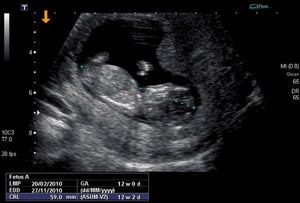

Antenatal diagnosis

and parental counseling

With the widespread use of prenatal ultrasound and the availability of fetal MRI (magnetic resonance image), more and more birth defects are diagnosed before childbirth. The pediatric surgeon, who is called for managing potentially surgical congenital anomalies just after the birth, has an important advisory role regarding the severity, the differentiated approach, and the final prognosis.

His participation in the antenatal counseling consultation is crucial for decision making, especially in unfavorable prognosis matters related to the termination of pregnancy or not. In antenatal counseling consultation is always necessary participation of relevant multiple involved specialties.